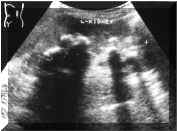

Staghorn

calculi

often

appear

as

multiple,

disconnected

within

the

collecting

system

(Picture2).

Sonography

generally

underestimates

extent

and

size

of

stones

in

patients

with

other

large

calculi.

presence

may

make

it

difficult

to

diagnose

underlying

hydronephrosis,

because

strong

acoustic

shadowing

from

Picture2.